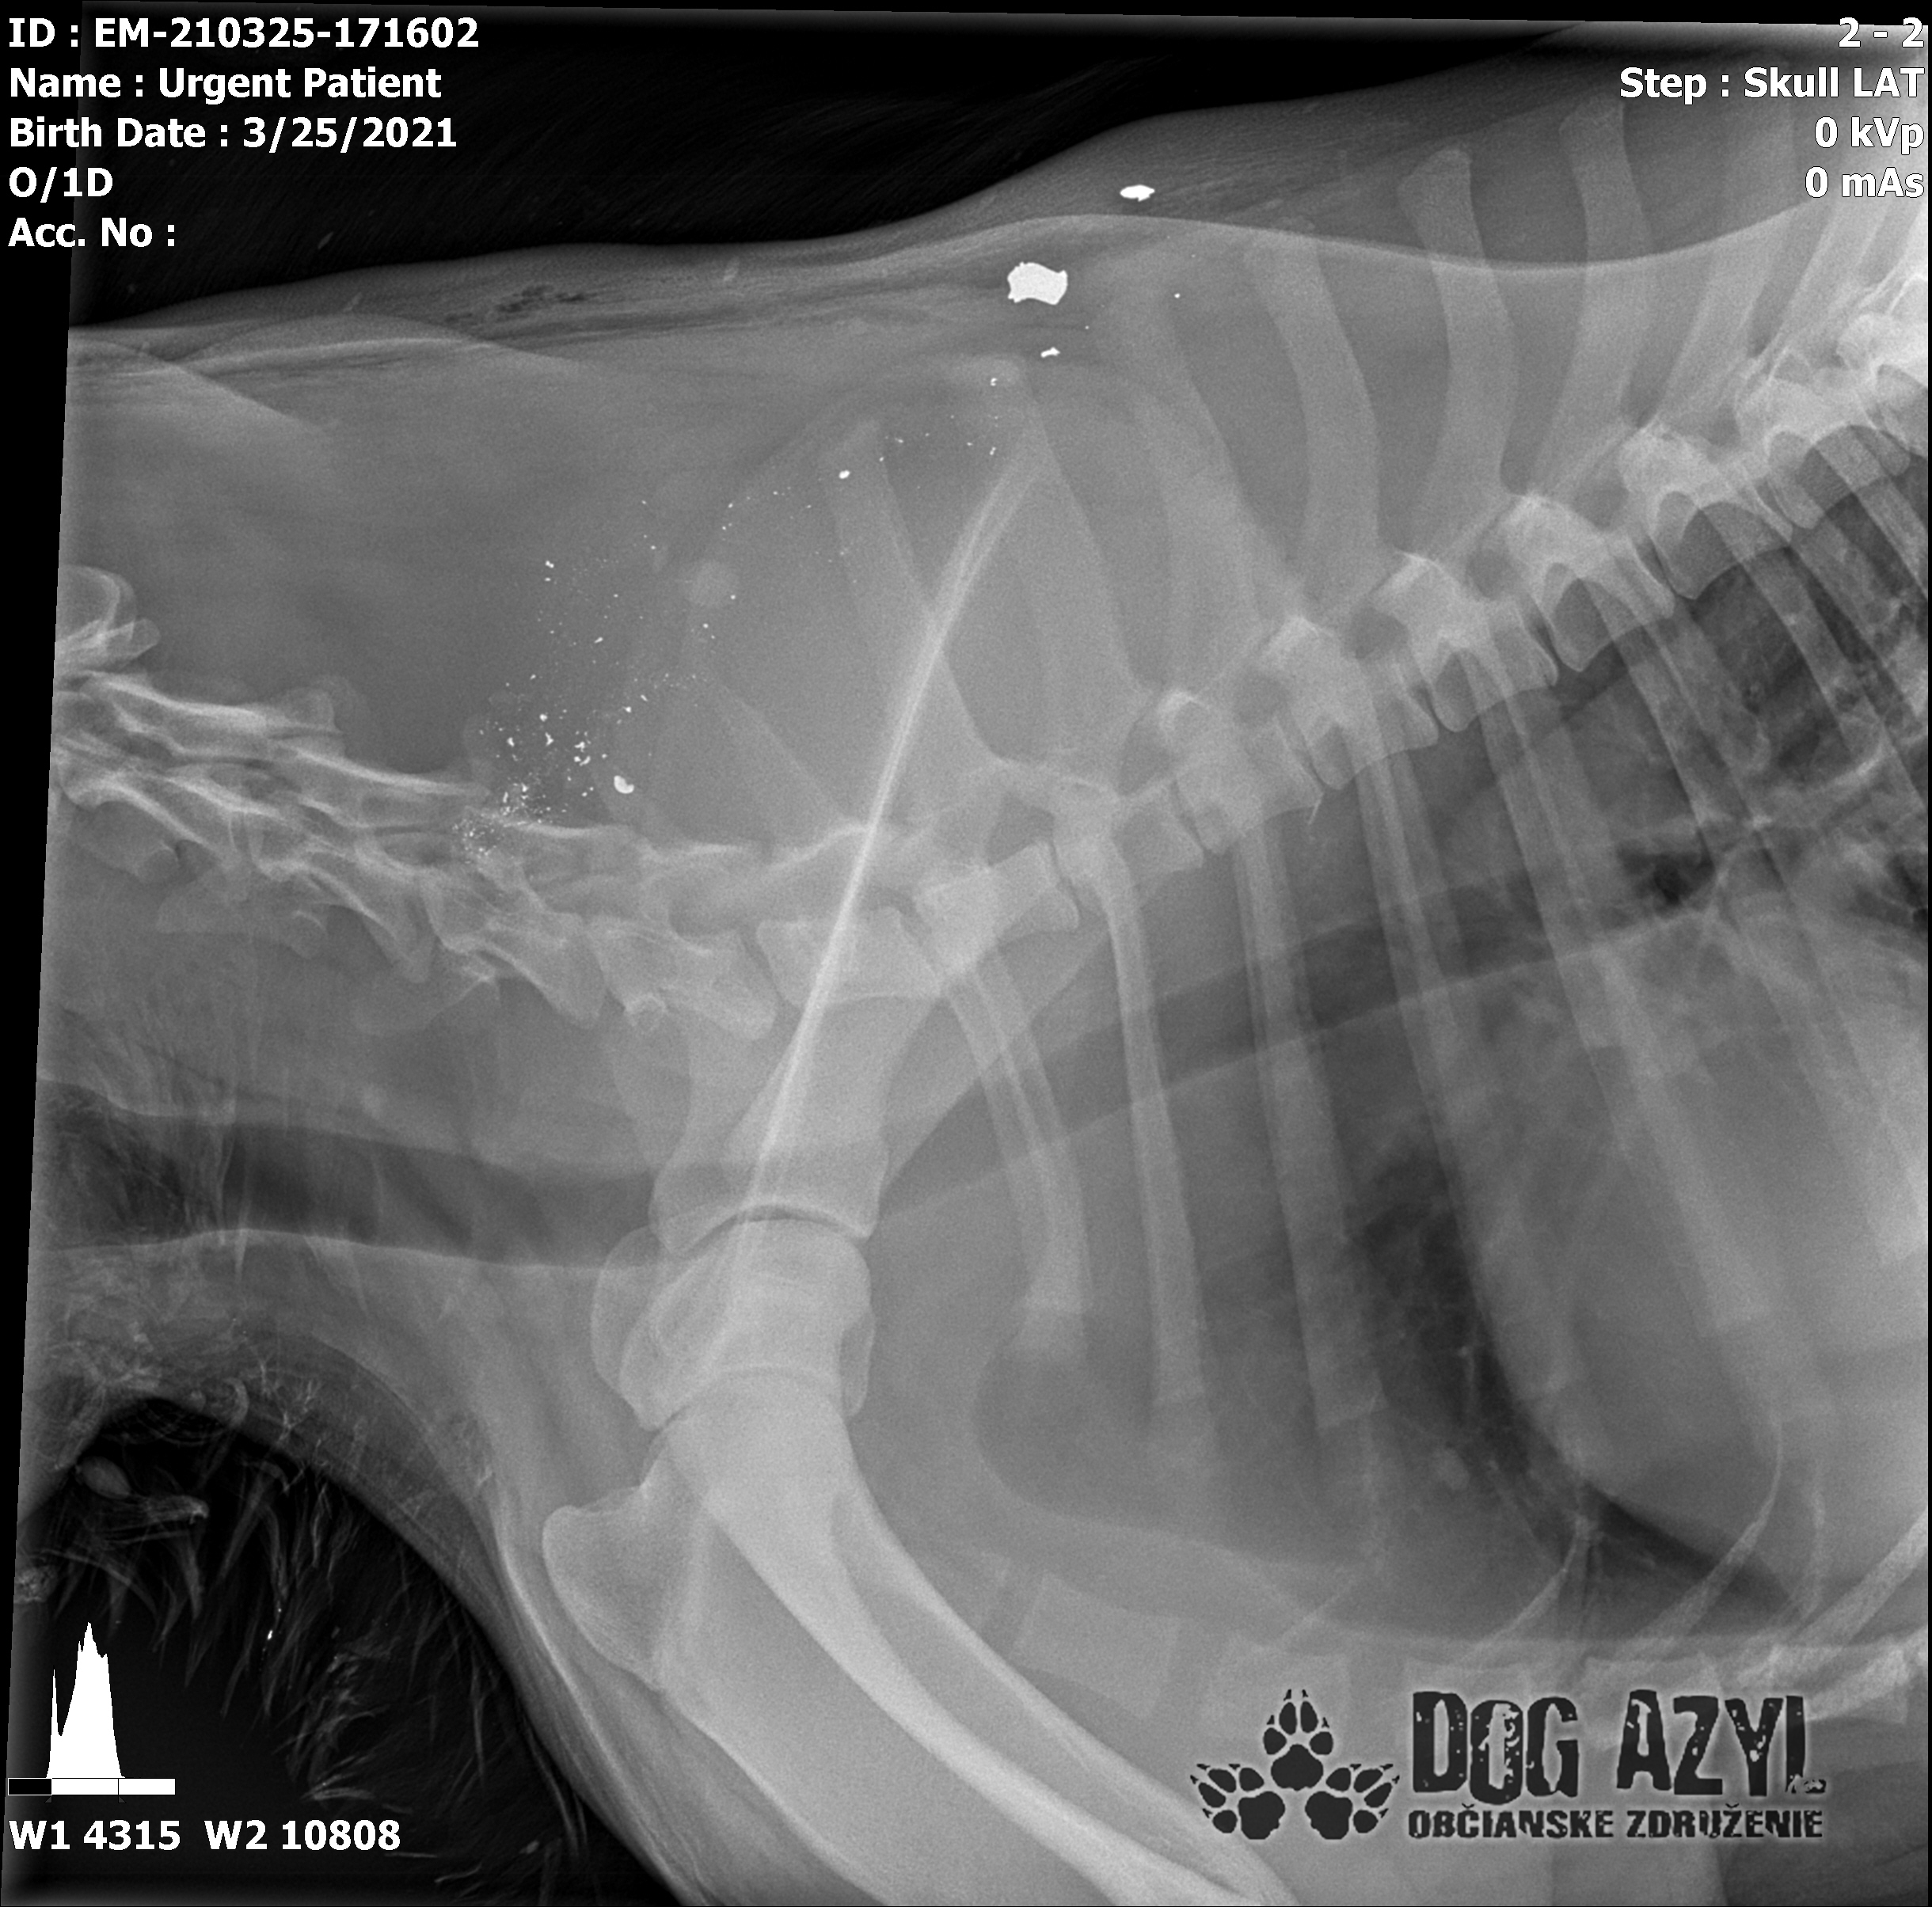

Ústami nevie pohnúť, jazyk si nevie ovládať a tak sa sám nedokáže schladiť ani napiť. Podľa RTG sú srdiečko a pľúca v poriadku, ale vôbec nemá vyhraté!!! Niekto chcel Barisa zlikvidovať, ale my za neho budeme bojovať do posledného dychu!!! Zajtra bude prevezený na veterinárnu kliniku Sibra centrum, kde ho čaká team špecialistov z oblasti chirurgie, neurológie a ortopédie. Ak je čo i len najmenšia nádej, že Baris bude môcť žiť, tak BARIS BUDE ŽIŤ!!!